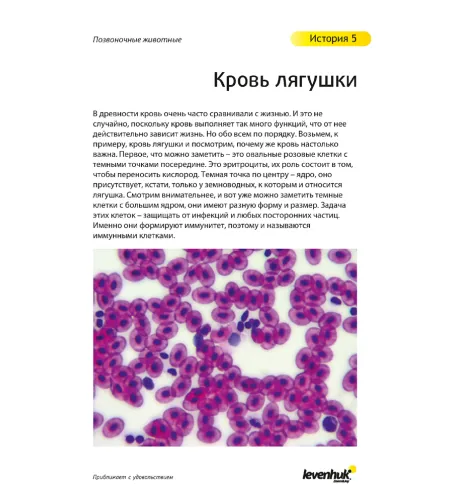

"See it all! Exploring the World Around Us" User Guide Sample Pages